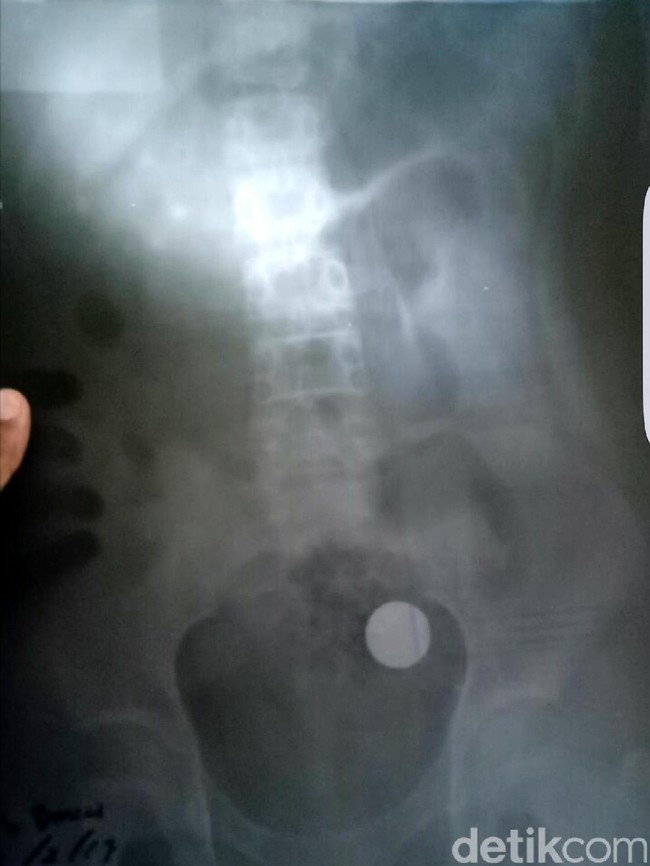

Jakarta - Sekeping uang logam ditemukan telah bersarang selama 4 tahun di usus seorang bocah di Sukabumi. Selain uang logam, ada sejumlah benda asing yang kerap terjebak lama dalam tubuh manusia.

Uang logam senilai Rp 500 ditemukan dalam usus Daniasis (13), putri kedua dari pasangan Marlis dan Elah di Sukabumi, Jawa Barat. Menurut pengakuan orang tua, uang logam itu tertelan sejak si bocah masih kelas 4 SD. Artinya, sudah 4 tahun uang tersebut bersarang di usus.